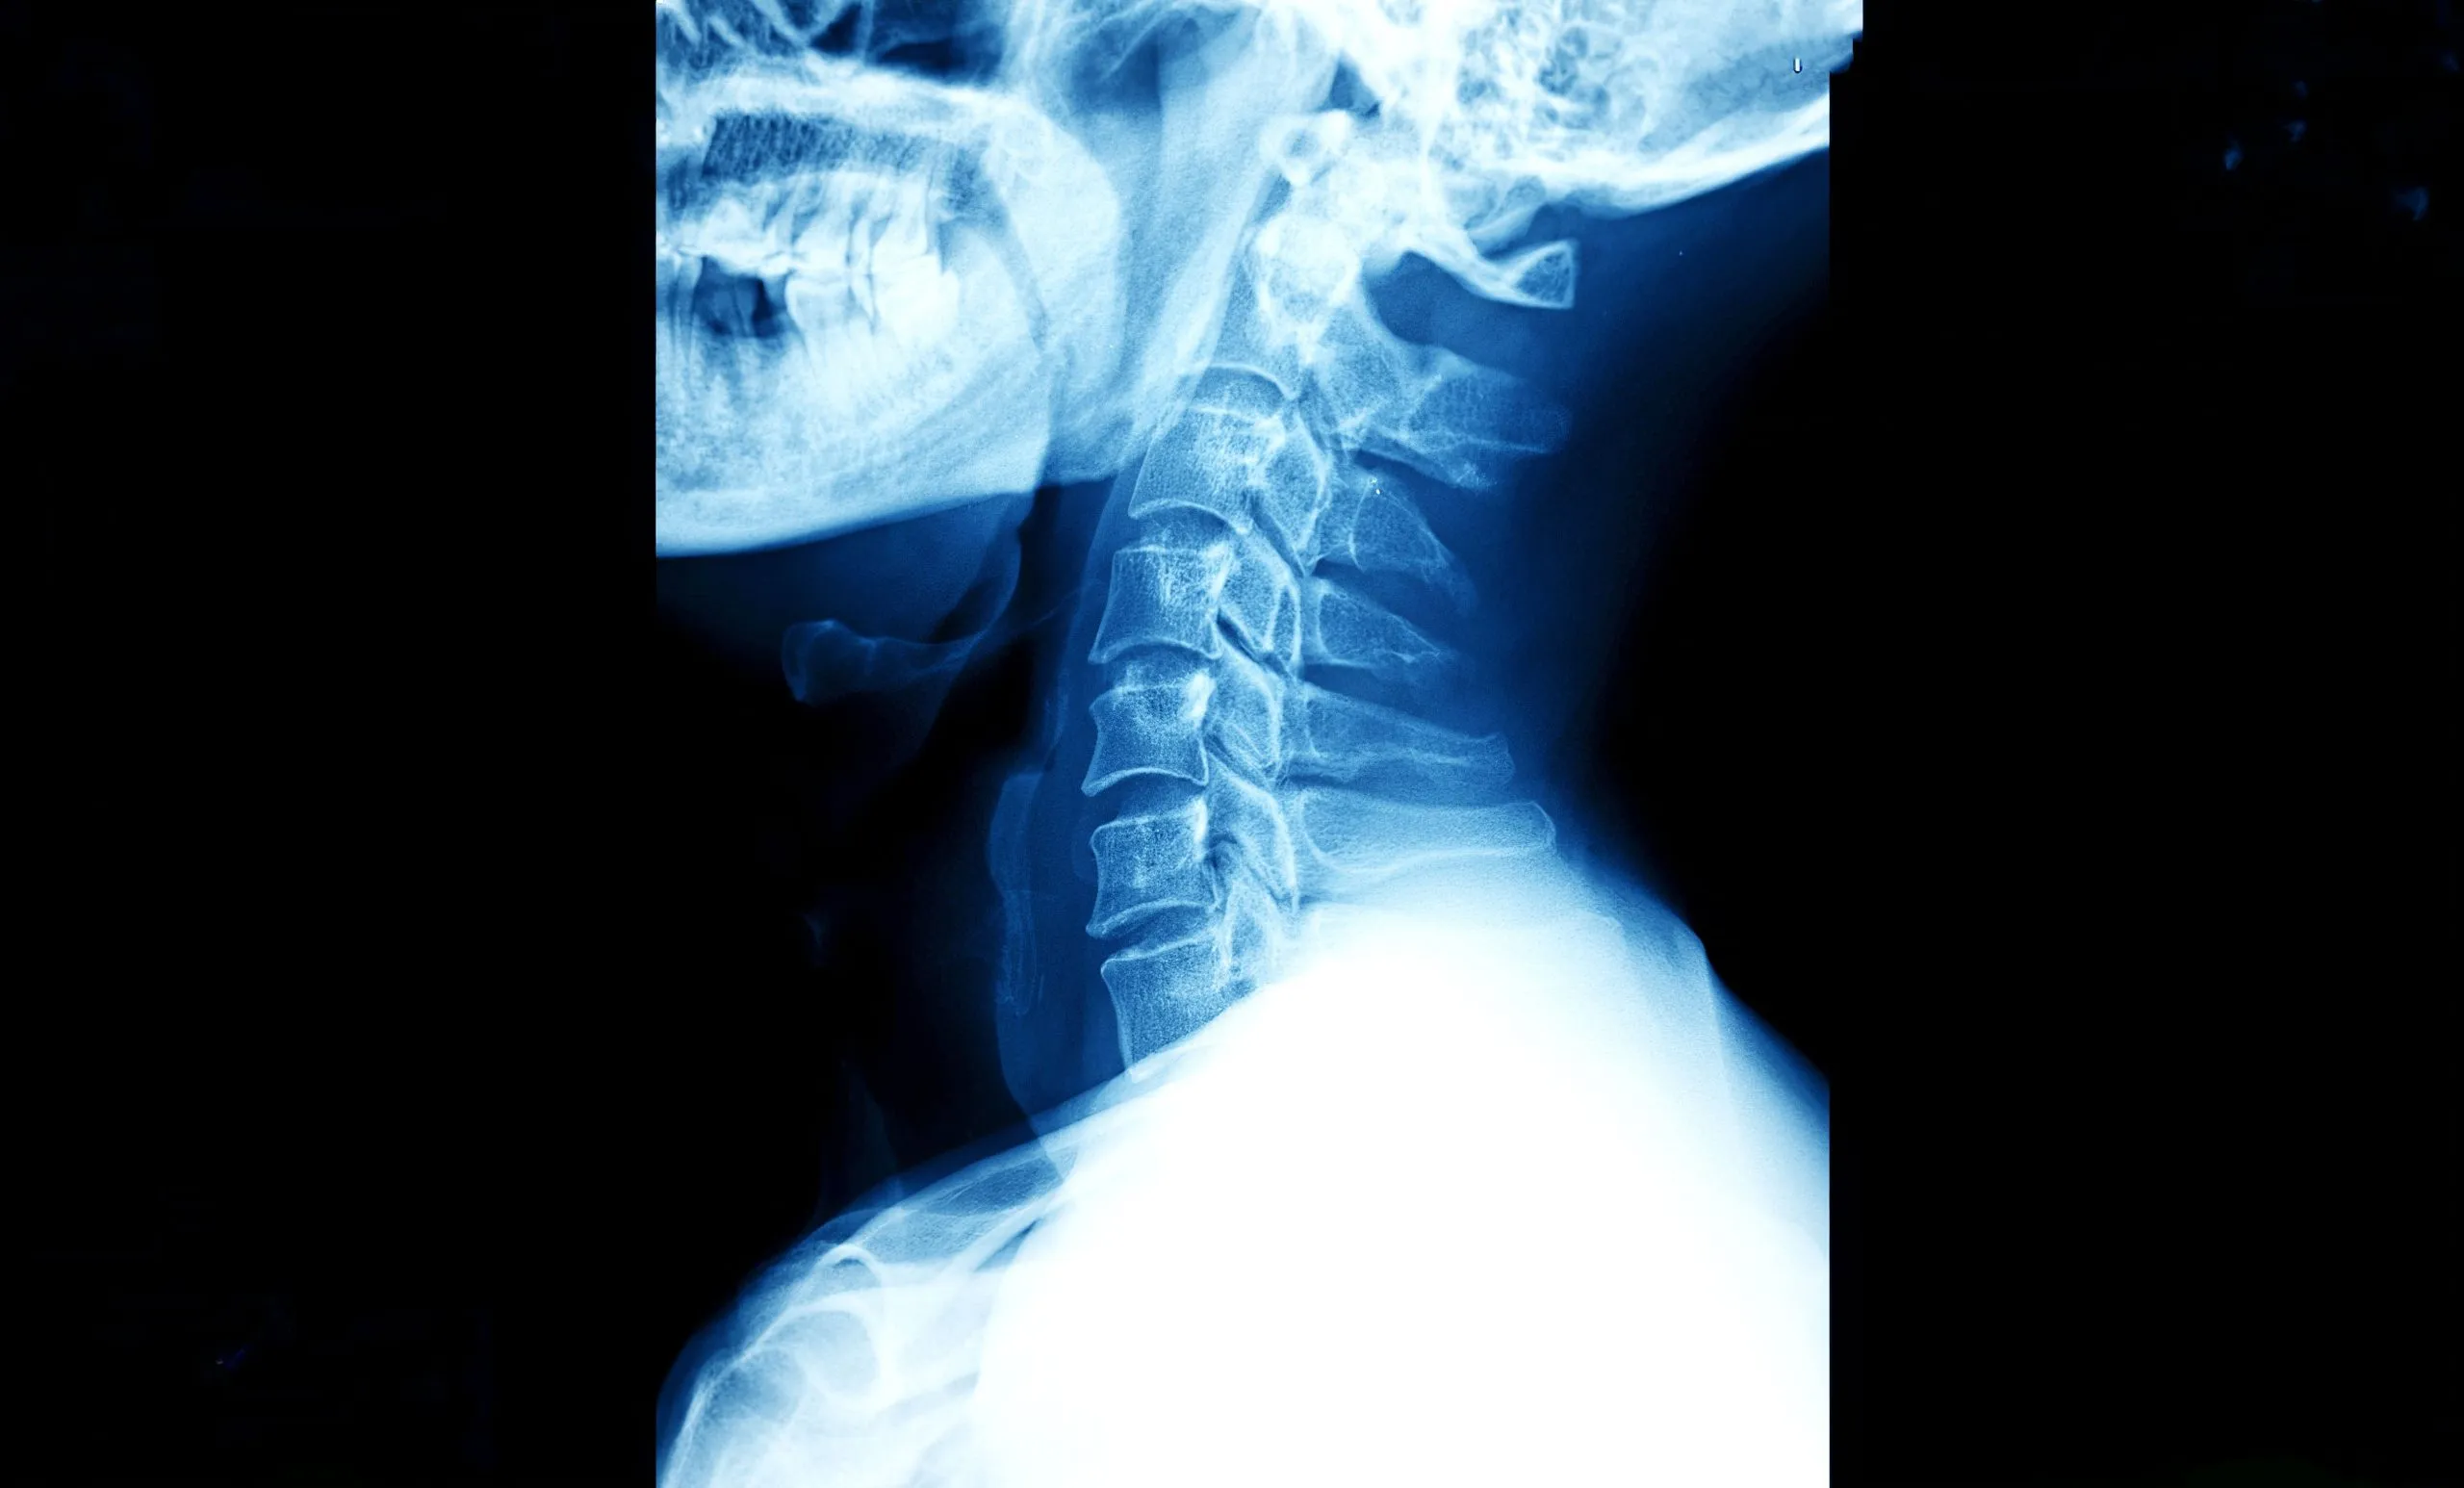

Neck surgery, also known as cervical spine surgery, refers to orthopedic procedures performed on the cervical spine. The seven vertebrae that make up the back of your neck run from the base of your skull to your clavicle. These procedures aim to address various issues affecting the cervical spine, including relieving pressure on nerves, correcting spinal deformities, or stabilizing damaged vertebrae.

The cervical spine is a remarkably complex and delicate structure.1 It must support the weight of your head, which typically weighs 10-12 pounds, while also allowing for an incredible range of motion. This combination of stability and flexibility makes the neck vulnerable to injury and degenerative changes over time.